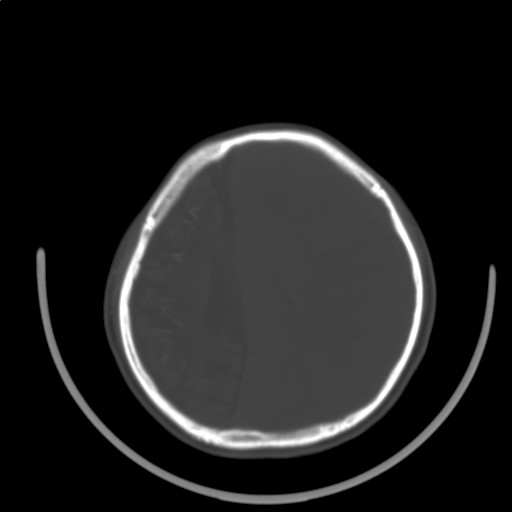

标题: PED3416:F,12Y,智力下降,学习成绩差,8个月时发过高烧。

右侧半球萎缩,软化,多量脑回样钙化,考虑颅面血管瘤病,建议dsa检查

右侧半球萎缩,软化,多量脑回样钙化,同侧颅盖板障增宽,考虑颅面血管瘤病,建议dsa检查与化脓性脑膜炎后遗改变鉴别。